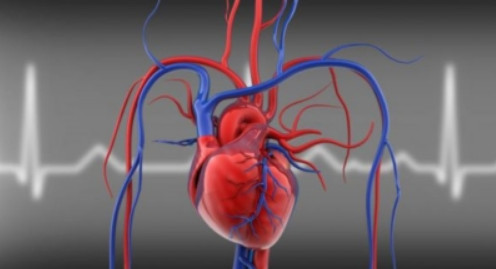

혈압은 혈맥이 혈관 벽을 향해 가해지는 압력을 말합니다. 피의 압력이 중요한 이유는 인체의 대부분의 기관들이 심장으로부터 나오는 혈액을 통해 산소와 영양분을 공급받아 기능을 발휘하기 때문입니다. 심장이 뛰었다 쉬었다를 반복하면서 적당한 혈압을 바탕으로 몸 안에 피가 순환이 되어야 모든 기능이 순조롭게 작동이 가능하지만 고혈압과 저혈압인 경우에는 이러한 순환에 문제가 생기면서 여러 신체 기관에도 문제가 생기기 시작합니다.

고혈압은 교감 신경에 의한 신경성 요인이나 유전, 흡연, 노령화 등의 원인으로 발생합니다. 동맥혈관 벽에 가해지는 혈액의 압력을 말하는 고혈압은 심장이 수축해서 동맥혈관으로 혈액을 보낼 때인 수축기 혈압과 심장이 이완되면서 혈액을 받아들일 때인 이완기 혈압의 수치를 정상수치에서부터 5가지 혈압의 범위로 나뉘어 그 심각성을 판단할 수 있습니다. 우리나라 성인 인구의 약 30%가 고혈압이 있는 것으로 추정되는데, 고혈압 환자의 90% 이상은 그 원인을 알 수 없는 경우가 대부분이라고 합니다.